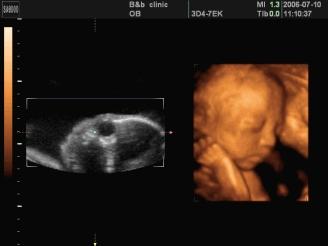

怀孕6个月,宝宝四维拍照嘴巴和鼻子都好大,生出来后是不是很丑

导读:怀孕期间 , 宝宝是在不断变化成长的 。 宝宝的相貌如何 , 基因在起作用 , 四维彩超拍出来宝宝丑 , 以后并不一定丑 。

怀孕6个月 , 宝宝的四维拍照嘴巴和鼻子都好大 , 生出来后是不是很丑?为什么?回答这个问题 , 我们可以分三点: